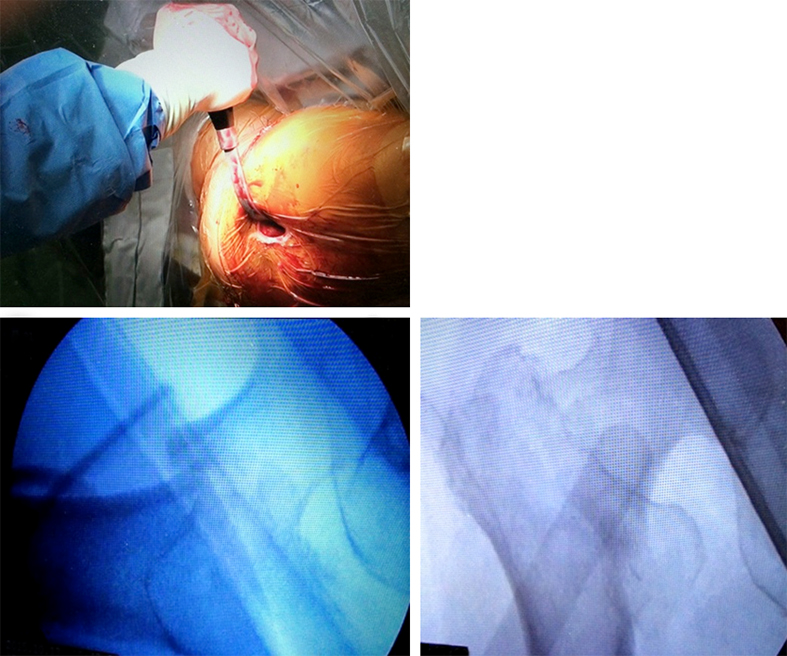

Case 3: Use of the hollow reamer in a clinical case

It is widely reported in the literature in Japan that there are many missed unstable femoral trochanteric fracture cases diagnosed only by x-ray, yet CT scans can clearly reveal the unstable fracture pattern.

A 77-year-old man suffered a right femoral trochanteric fracture (Figs 5-8). This case can be diagnosed as AO31-A1. However, the CT shows the detachment of the lesser trochanter (AO31-A2). Precise information of dangerous fracture patterns in advance might simplify the imaging of intraoperative reduction maneuvers and the use of the implants.

In this case, the fracture lines are located in the area of the intended nail insertion point. The 3-D reconstruction images distinctly show that the hollow reamer prevented the fracture fragments from being pushed apart when introducing the hollow reamer close to the fracture line.